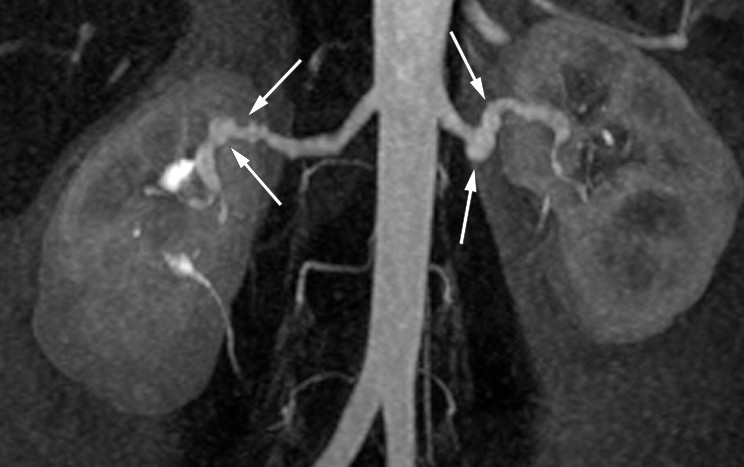

Uavhengig av kargebet er patologiske forandringer ved fibromuskulær dysplasi funnet i alle tre lag av arterieveggen (tunica intima, media og externa/adventitia; se figur 1). Forandringene består av bindevevsdannelse og/eller hyperplasi av glatte muskelceller. I 2012 la en europeisk ekspertgruppe frem en forenklet subklassifisering basert på angiografiske funn: multifokal («string-of-beads»), tubulær (stenoser ≥ 1 cm lengde) eller unifokal type (stenose < 1 cm lengde) (6). Siden skillet mellom unifokal og tubulær type var basert på stenosens lengde, ble det anbefalt å samle disse typene under betegnelsen unifokal. Multifokal manifestasjon med alternerende dilatasjon og konstriksjon av arterien utgjør over 80 % av tilfellene av renal fibromuskulær dysplasi (2). Multifokal type er klassisk for fibromuskulær dysplasi, mens den unifokale kan være vanskeligere å skille fra andre årsaker til karanomalier (figur 2 og 3). I nyrearterien er det uavhengig av subtype de midtre og distale deler av karet som affiseres, og hos 60 % av pasientene er affeksjonen bilateral (4). Aneurismer og disseksjon i nyrearterien kan forårsake nyreinfarkter (7) og er beskrevet hos henholdsvis 5,6 % og 4,3 % (2).

Kateterbasert digital subtraksjonsangiografi er diagnostisk gullstandard (14), men benyttes hovedsakelig som ledd i behandling med angioplastikk. Aktuelle undersøkelsesmetoder er ultralyd med doppler og CT- og MR-angiografi av nyrearteriene. Ultralyd kan påvise økte blodhastigheter i nyrearterien og endringer i dopplersignalene i nyrene. Metoden er billig og lite invasiv, men har lav sensitivitet, derfor gjøres ofte CT- og MR-angiografi, som har høyere sensitivitet og spesifisitet (15, 16), spesielt for multifokal fibromuskulær dysplasi (17).

CT-angiografi er mer presis og har bedre oppløsning enn MR-angiografi, spesielt ved lesjoner distalt i nyrearterien og i hilus, og egner seg bedre til differensiering mellom aterosklerotiske og ikke-aterosklerotiske forandringer (17). Til MR-angiografi benyttes ikke potensielt nefrotoksisk kontrastmiddel.